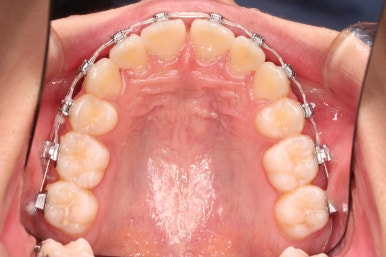

1. 초진 시 입안의 모습 평가

부산치아교정치과 키다리아저씨치과에 처음 내원했을 당시의 입 안의 모습입니다.

전반적으로 윗니가 나와있는 양상이고요.

위아래 앞니쪽이 삐뚤어져 있는 상태였습니다.

우선 윗니만 장치를 부착했습니다.

순서는 윗니 장치 부착 후 발치를 하고, 가지런하게 된 뒤에, 과개교합 개선을 위한 특별한 장치가 들어가면서 아랫니에도 브라켓을 부착하기로 정했습니다.

위아래 치열이 매우 고르게 되었으며, 이제부터는 발치공간을 줄여나가면서 교합을 맞춰 나가면 됩니다.

부산치아교정치과 키다리아저씨치과에서 마무리한 입안의 모습입니다.

가지런하게 잘 정렬이 되었고요.

윗니만 발치한 편악발치교정이지만 틈새 없이 공간이 닫혔으며 교합도 잘 맞습니다.

위아랫니가 가지런하게 보기 좋게 배열이 되었고요.